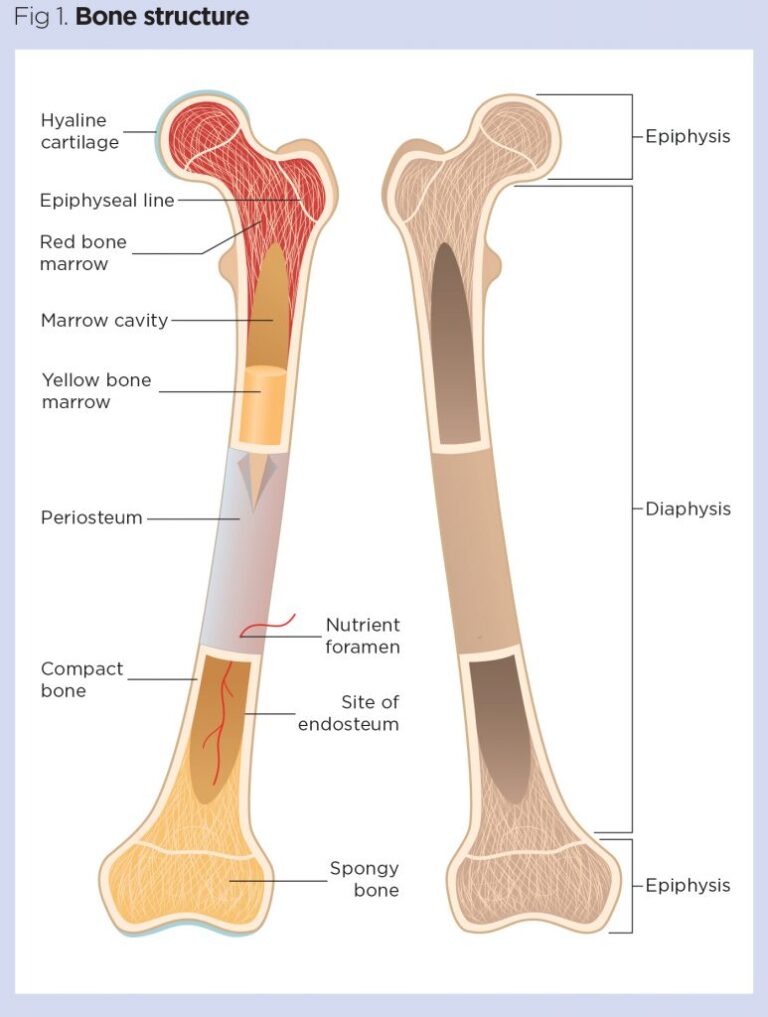

The main portion of a bone or shaft is called the “diaphysis”. The medullary cavity, or marrow cavity, is the space inside the diaphysis.

The marrow cavity is covered by a layer of endosteum, which contains cells necessary for bone development. The ends of the bone are called the “epiphyses”.

The region of mature bone where the diaphysis joins each epiphysis is called the “metaphysis.”

The epiphyses are covered by articular cartilage. Cartilage is a semirigid form of connective tissue that helps to reduce friction and absorbs some of the shock in synovial joints.

The periosteum is a membrane covering the surface of bones, except at the articular surfaces. The periosteum is composed of two layers, an outer fibrous layer and an inner highly vascular layer that contains cells for the creation of new bones. The periosteum is the point where ligaments and tendons get attached and is critical for bone growth, repair, and nutrition.